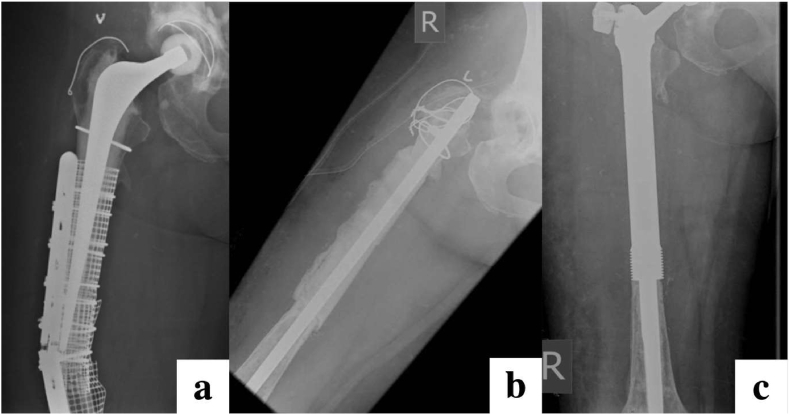

Fig. 6.

Radiographs of an elderly patient presenting with an infected periprosthetic fracture (a) undergoing two-stage revision with an antibiotic cement-coated nail ‘cementoplasty’ at first-stage (b), followed definitive proximal femoral replacement at second-stage.(c).